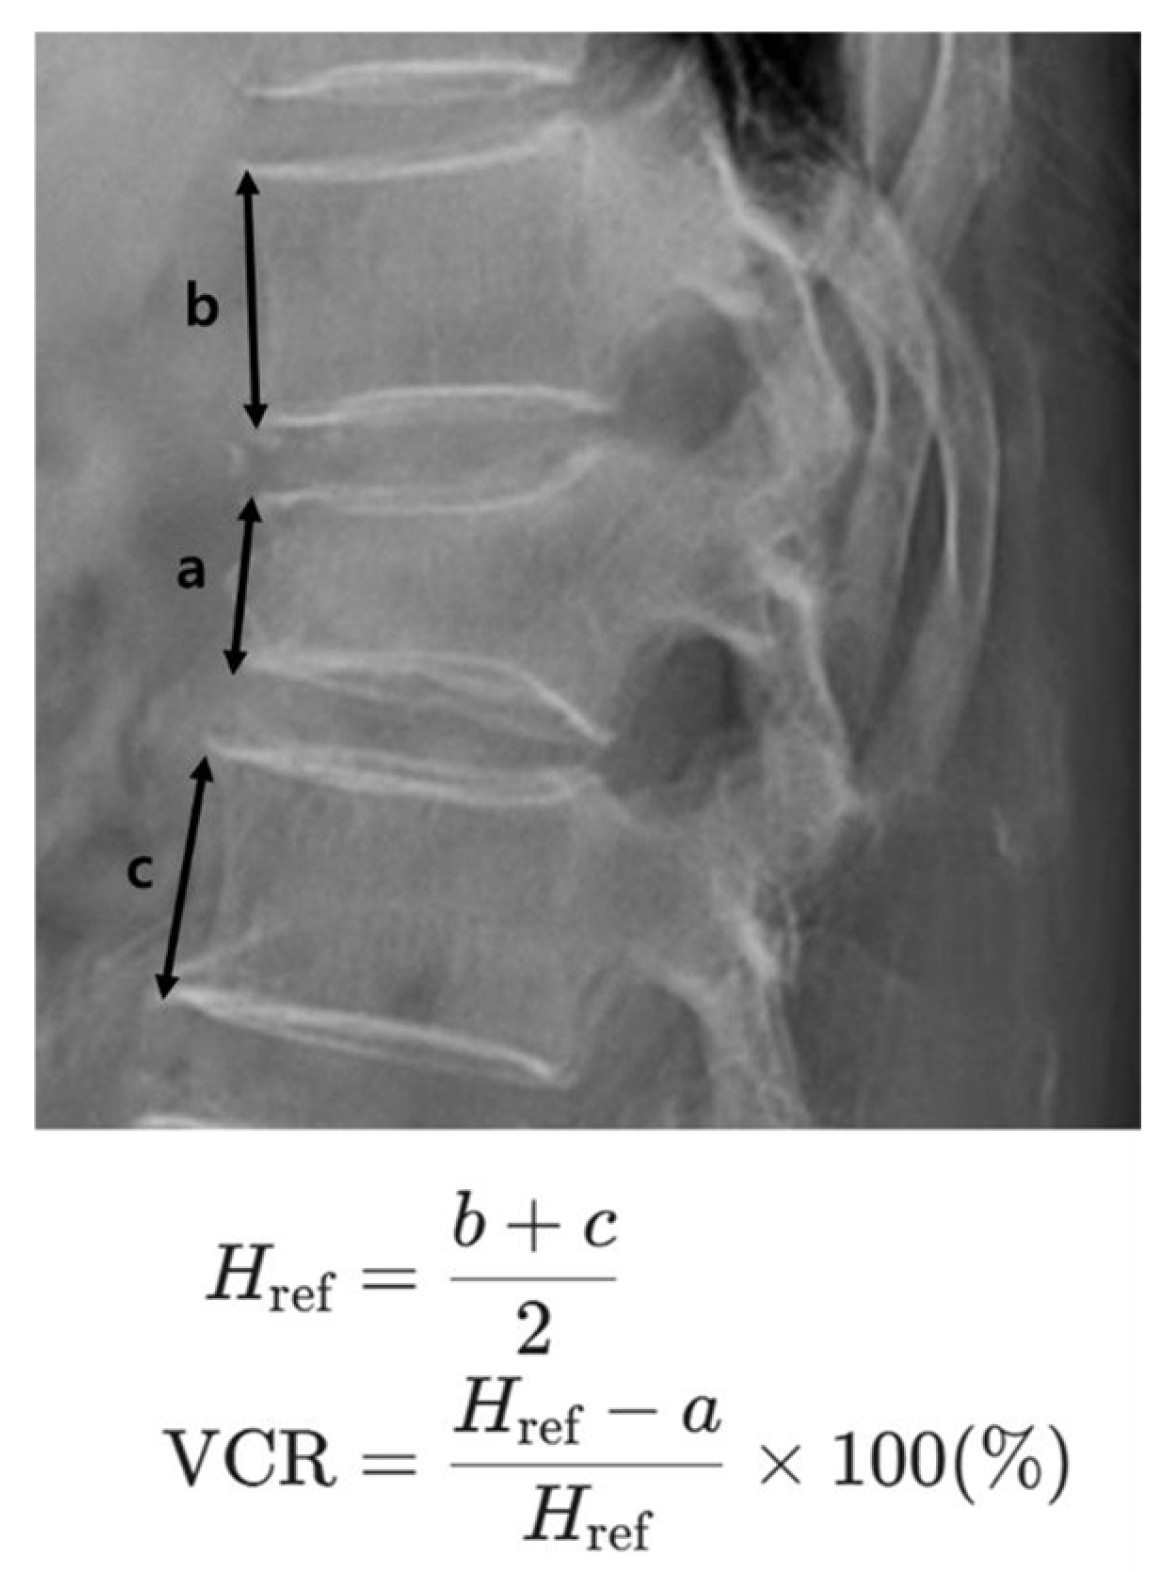

On each radiograph, the anterior height (AH) of the fractured vertebral body was measured. To calculate the vertebral compression rate (VCR), this value was compared to a reference height. This reference height was determined by averaging the anterior heights of the vertebrae directly above and below the fractured one. The VCR was then calculated as the percentage loss of height of the fractured vertebra relative to this reference height. Thus, a higher VCR value indicates a more severe loss of anterior vertebral height (Figure 1).

Figure 1. Measurement of the Vertebral Compression Rate (VCR). The anterior vertebral height of the fractured body is measured as a. The anterior heights of the adjacent superior and inferior vertebral bodies are measured as b and c, respectively. The reference height (Href) is calculated as the average of the adjacent vertebral heights [Href = (b + c)/2]. The VCR is then calculated using the formula: VCR (%) = (1 − a/Href) × 100, representing the percentage of height loss relative to the estimated normal height.